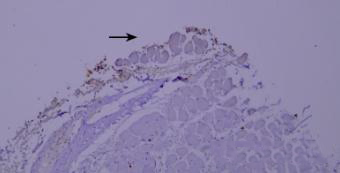

染色液的堆积(黑色箭头区域)。

优化建议:

充分洗涤。

7.干片

干片导致的假阴性(黑色箭头区域)。

加入Tween-20的缓冲液能够更好地防止切片干燥。

8.边缘效应

边缘效应造成的非特异性染色(黑色箭头区域)。

组织切片与玻片黏贴牢固,试剂完全覆盖组织防止干片,加入Tween-20的缓冲液能够更好地防止边缘效应。